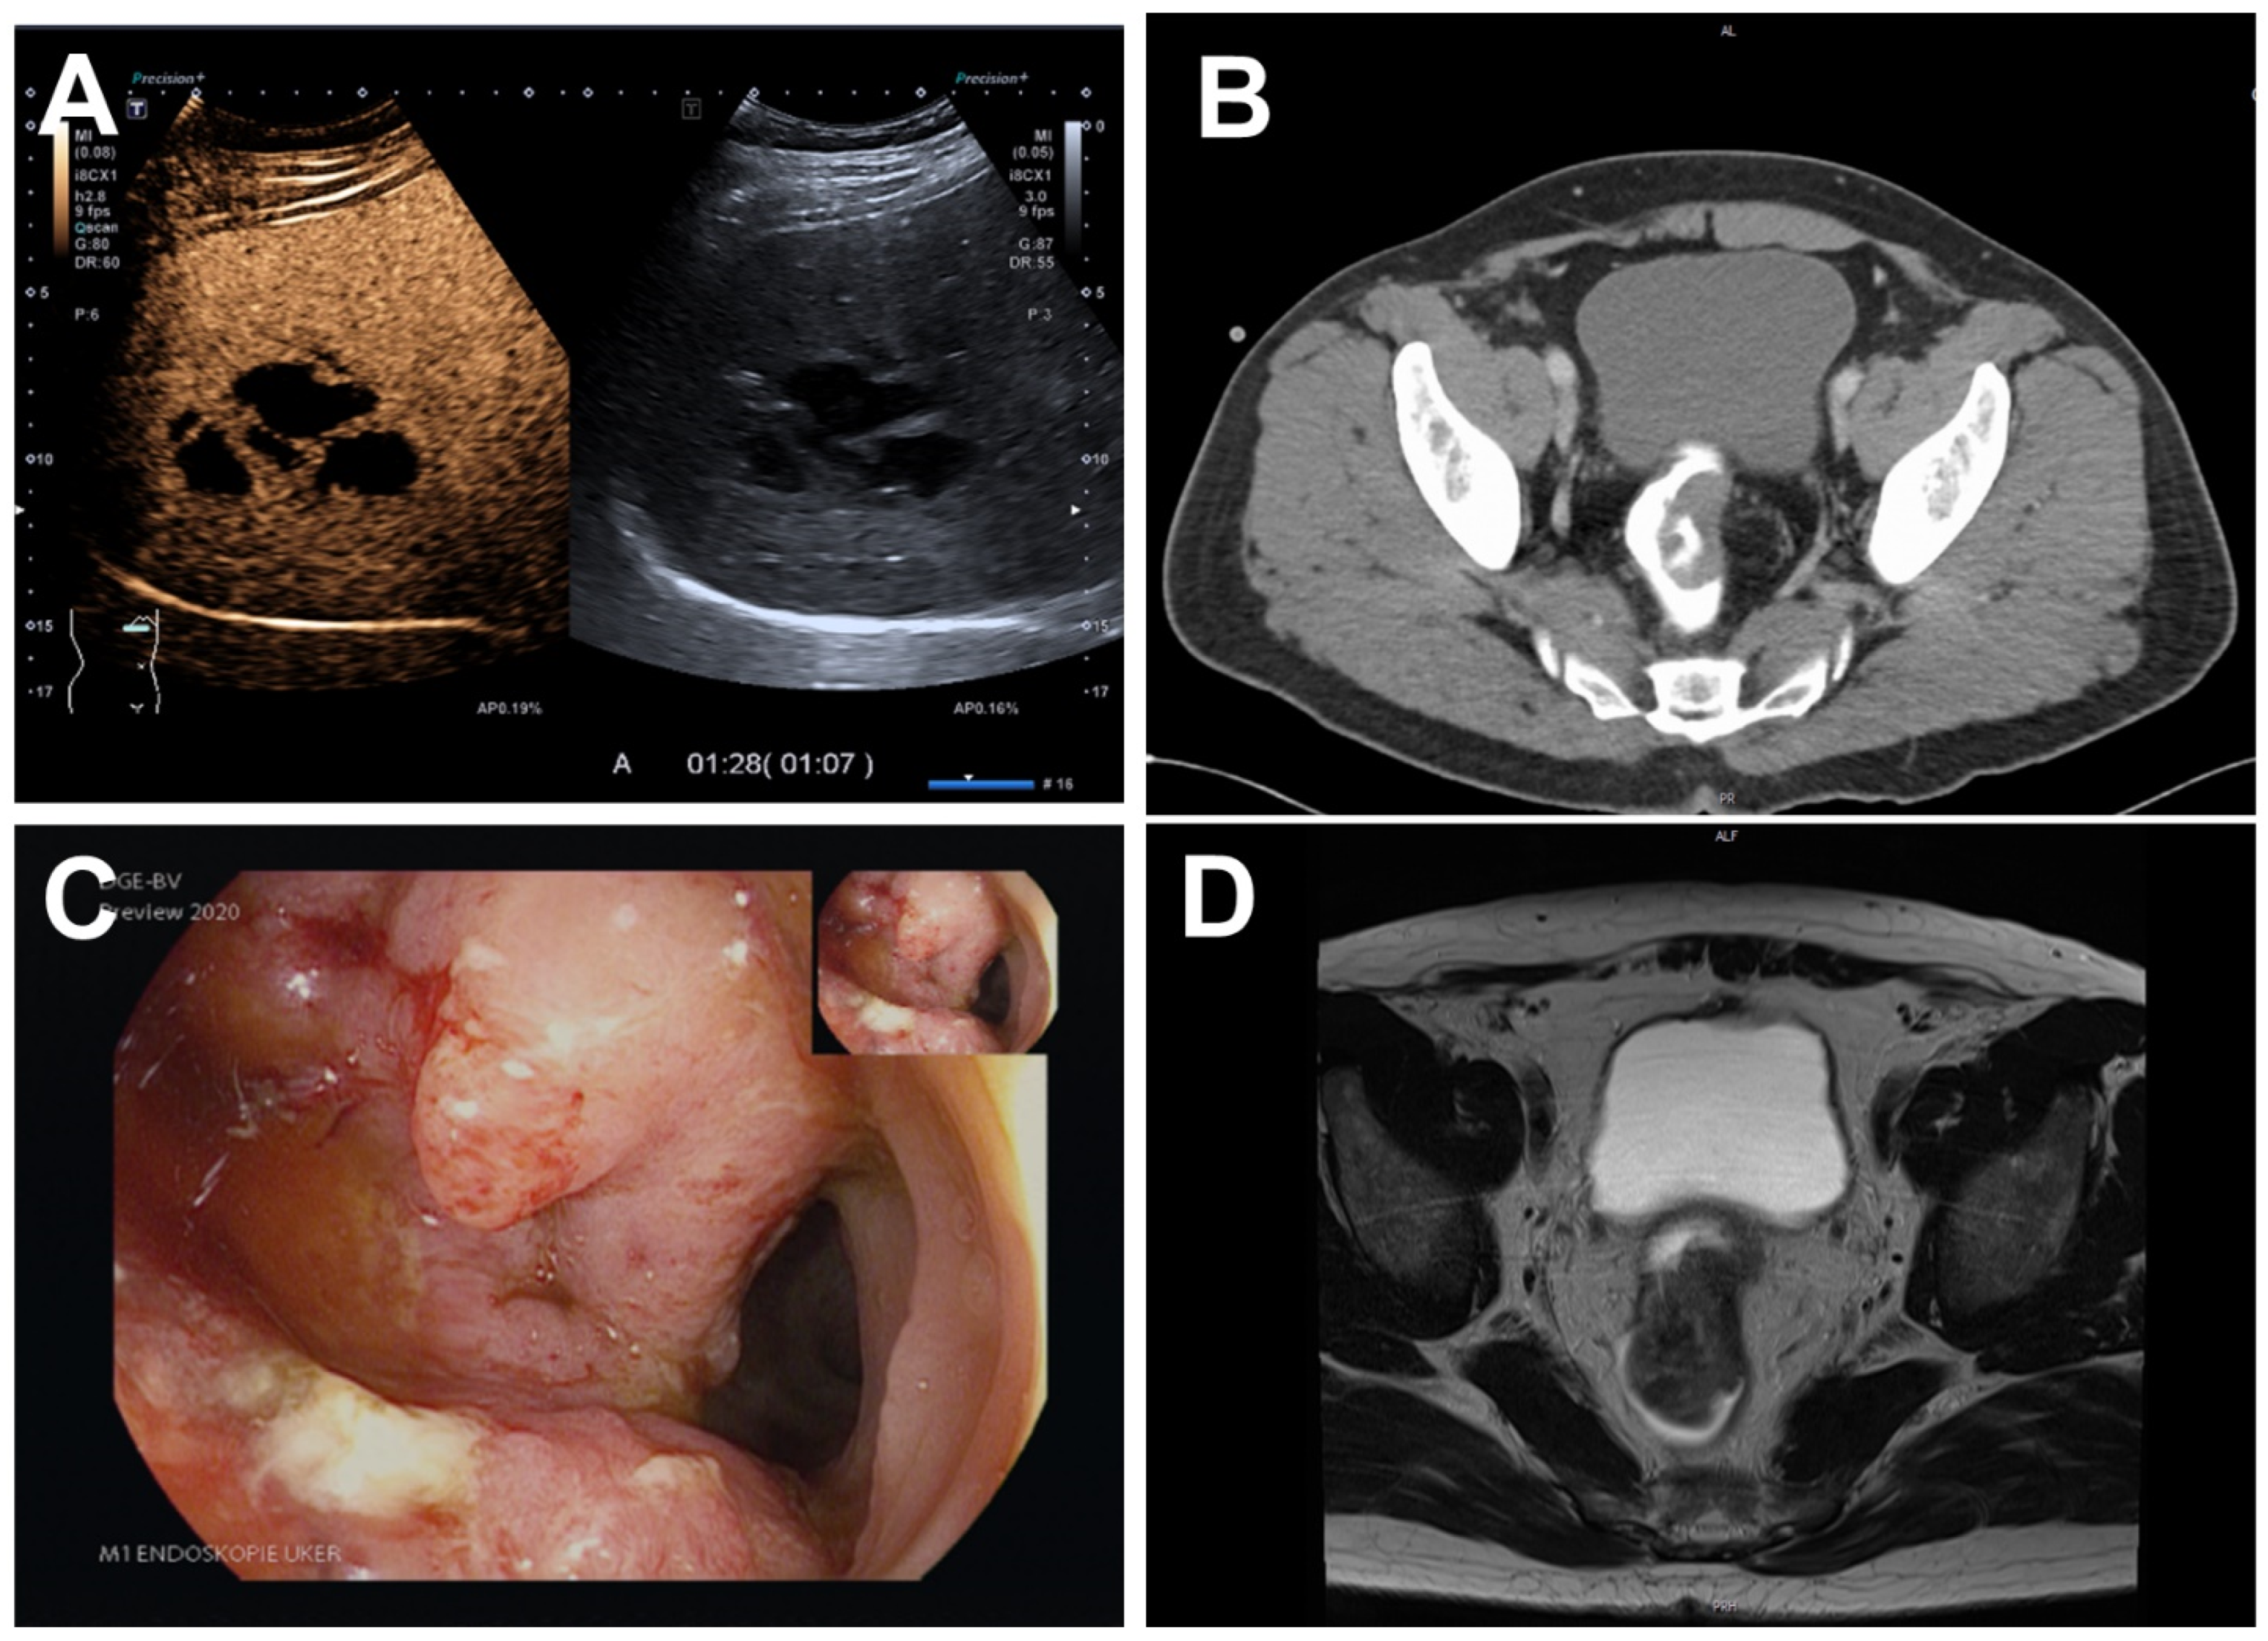

Rectal Cancer Presenting with Absceding Infection Due to Fusobacterium nucleatum

2. Case Report